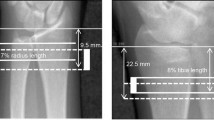

Though still a topic of debate, the position that skeletal health is compromised with obesity has received support in the pediatric and adult literature. The limited data relating specifically to trabecular bone microarchitecture, however, have been relatively inconsistent. The aim of this pilot cross-sectional case-control study was to compare trabecular bone microarchitecture between obese (OB) and normal-weight (NW) late-adolescent females. A secondary aim was to compare diaphyseal cortical bone outcomes between these two groups. Twenty-four non-Hispanic white females, ages 18–19 years, were recruited into OB (n = 12) or NW (n = 12) groups based on pre-specified criteria for percent body fat (≥32 vs. <30, respectively), body mass index (>90th vs. 20th–79th, respectively), and waist circumference (≥90th vs. 25th–75th, respectively). Participants were also individually matched on age, height, and oral contraceptive use. Using magnetic resonance imaging, trabecular bone microarchitecture was assessed at the distal radius and proximal tibia metaphysis, and cortical bone architecture was assessed at the mid-radius and mid-tibia diaphysis. OB versus NW had lower apparent trabecular thickness (radius and tibia), higher apparent trabecular separation (radius), and lower apparent bone volume to total volume (radius; all P < 0.050). Some differences in radius and tibia trabecular bone microarchitecture were retained after adjusting for insulin resistance or age at menarche. Mid-radius and mid-tibia cortical bone volume and estimated strength were lower in the OB compared to NW after adjusting for fat-free soft tissue mass (all P < 0.050). These trabecular and cortical bone deficits might contribute to the increased fracture risk in obese youth.

Modlesky CM, Subramanian P, Miller F (2008) Underdeveloped trabecular bone microarchitecture is detected in children with cerebral palsy using high-resolution magnetic resonance imaging. Osteoporos Int 19(2):169–176

Modlesky CM, Majumdar S, Dudley GA (2008) Trabecular bone microarchitecture in female collegiate gymnasts. Osteoporos Int 19(7):1011–1018

Modlesky CM, Kanoff SA, Johnson DL, Subramanian P, Miller F (2009) Evaluation of the femoral midshaft in children with cerebral palsy using magnetic resonance imaging. Osteoporos Int 20(4):609–615